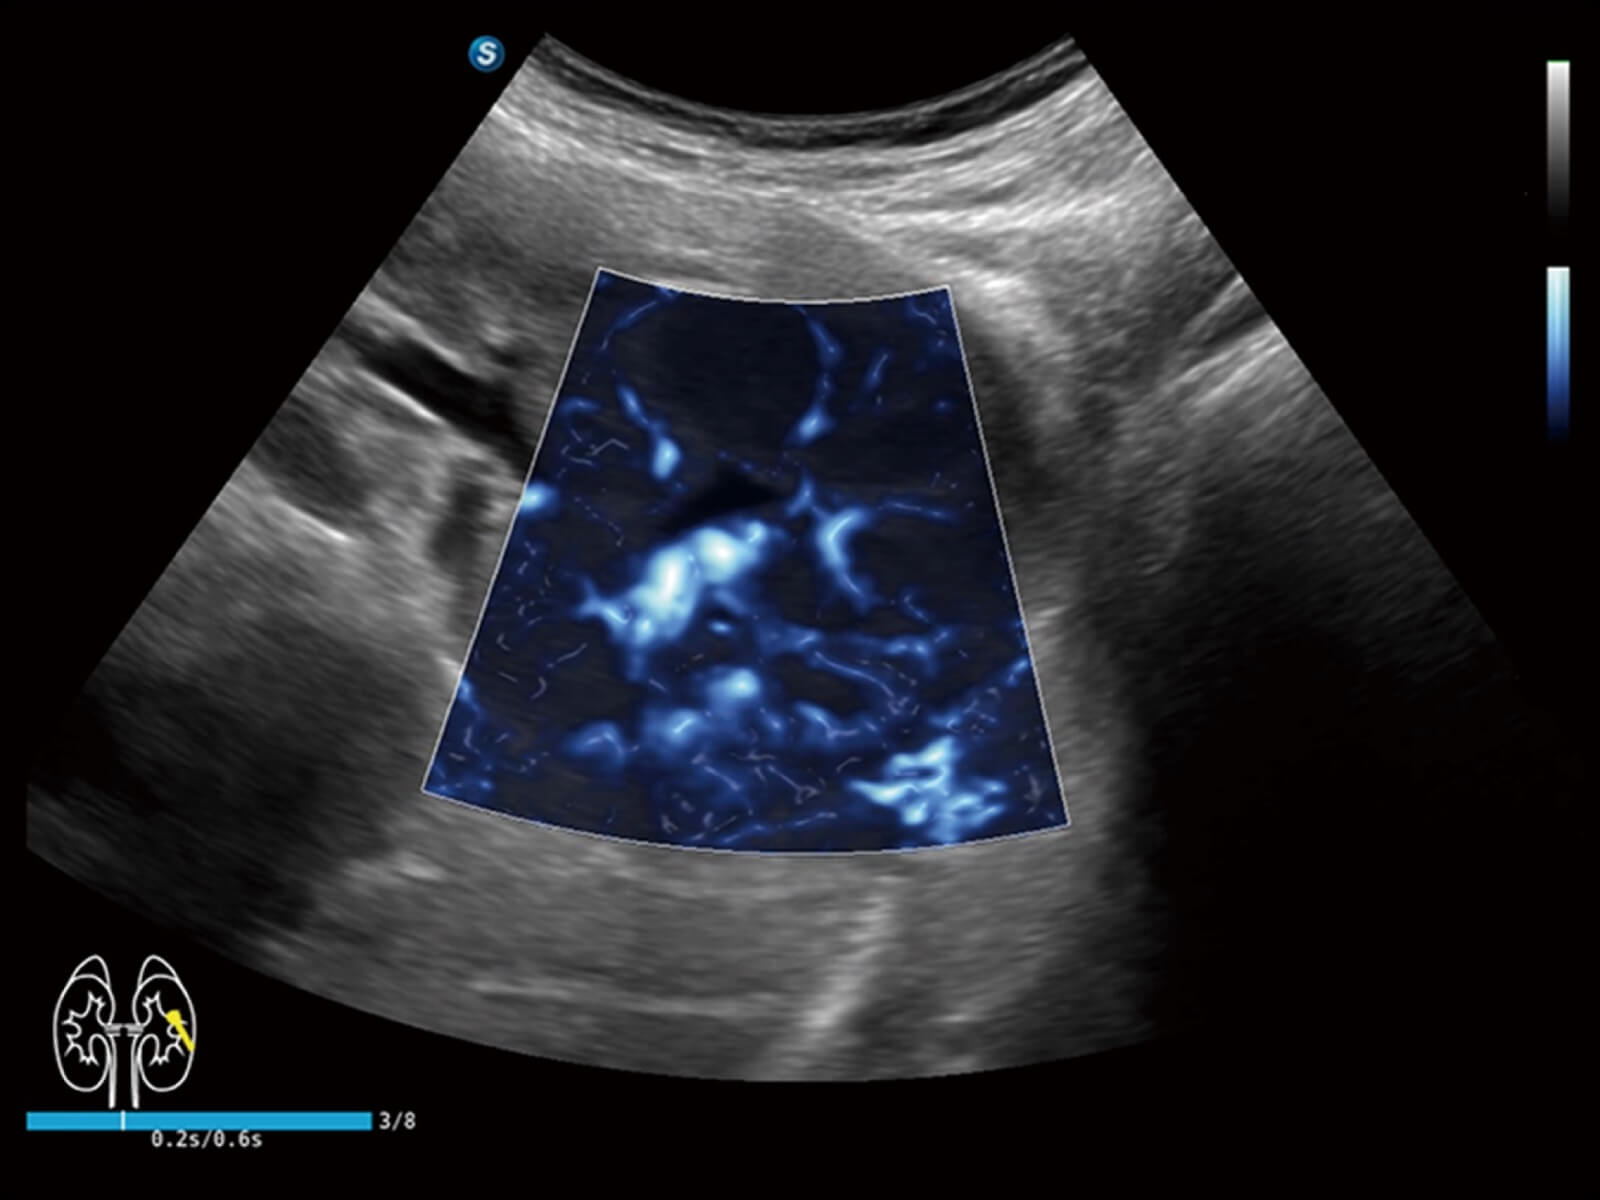

Bright Flow立体血流成像

通过光照模型,使二维血流显示出立体的效果,增加血流的敏感性、成束性,减少外溢。可以和其他不同的血流技术联合使用,轻松应对微小血管,增强血流的立体效果,提升视觉敏感性。